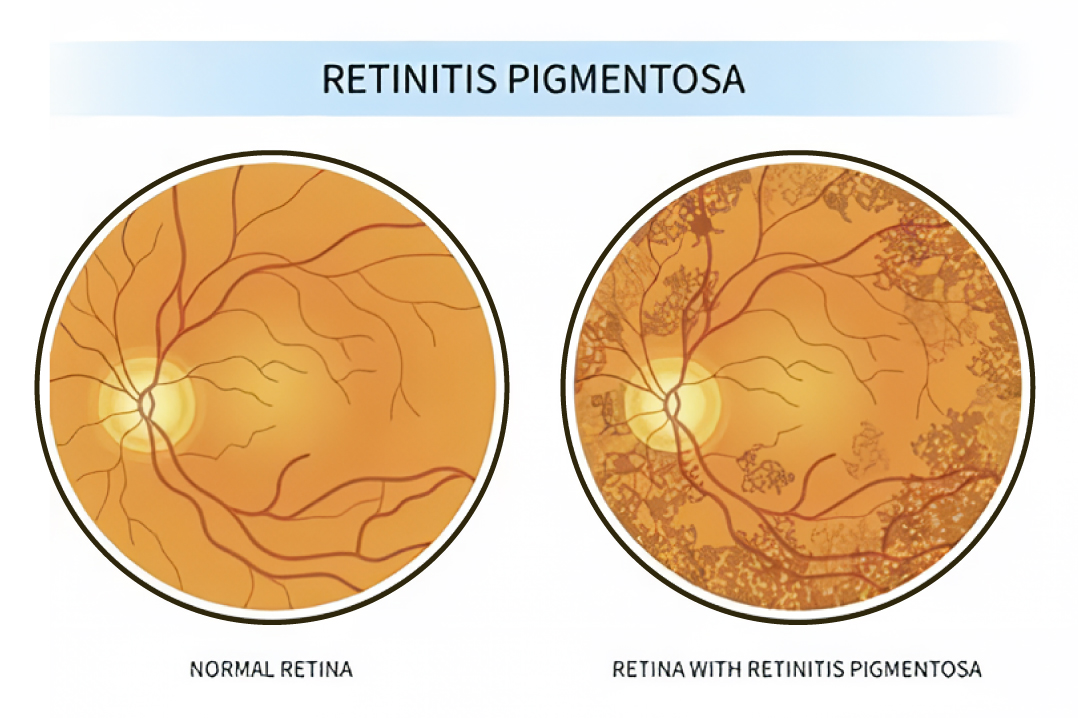

视网膜色素性病变 (RP)

视网膜色素变性 (RP) 是一组遗传性疾病,会逐渐损害视网膜,即眼睛后部的感光组织,导致视力逐渐下降。这种遗传性视网膜疾病的特征是感光细胞和视网膜色素上皮功能逐渐丧失,通常在青春期发病,影响双眼。最初的症状通常是夜盲,随后是视野缩小,形成“隧道视野”效应。特征性体征包括视网膜上出现深色骨针状色素沉积、视盘蜡黄色苍白、后极部出现金黄色光泽以及视网膜血管均匀变细,最终由于视神经萎缩导致严重视力丧失或失明。RP的遗传基础复杂,具有多种遗传模式,包括常染色体显性遗传、常染色体隐性遗传和X连锁隐性遗传,该疾病分为典型和非典型两种类型。虽然RP目前无法治愈,但现代医学西医治疗的重点是减缓其进展并管理相关并发症。

中医称本病为“高风内障”,认为RP的病因主要是先天不足、视网膜血管阻塞和视力减弱,可分为肾阳虚、肝肾阴虚和脾气虚等证型。中医理论基于辨证论治,结合中药和针灸等个性化调理原则,旨在解决潜在的失衡,从而可能稳定病情、减缓其进展并改善部分患者的视功能。